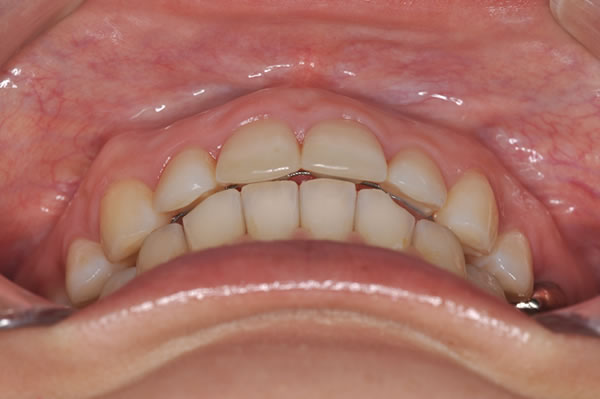

上顎前突症の治療例

上顎前突症(出っ歯)の矯正症例 ケース01

| 治療前(初診) | 治療後 | |